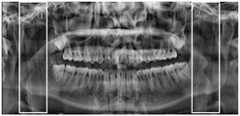

fig. 3 is an overall view of a weakened cheek portion of a specific example of a pixel-adjustment-based cheek clip development weakening method in an embodiment of the present invention;

Illustratively, the pixels of each column of the cheek clamp region are adjusted by using the obtained pixel adjustment value of each column of each cheek clamp region, and a development weakening panoramic image after adjustment of the cheek clamp region is obtained, as shown in fig. 3.